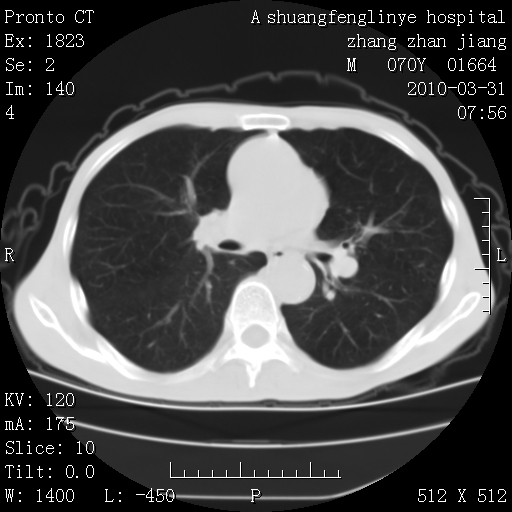

双上肺继发型tb并左上空洞形成,主动脉冠脉钙化。

1)两肺上叶继发性肺结核并左肺上叶空洞形成。2)冠状动脉及主动脉钙化。